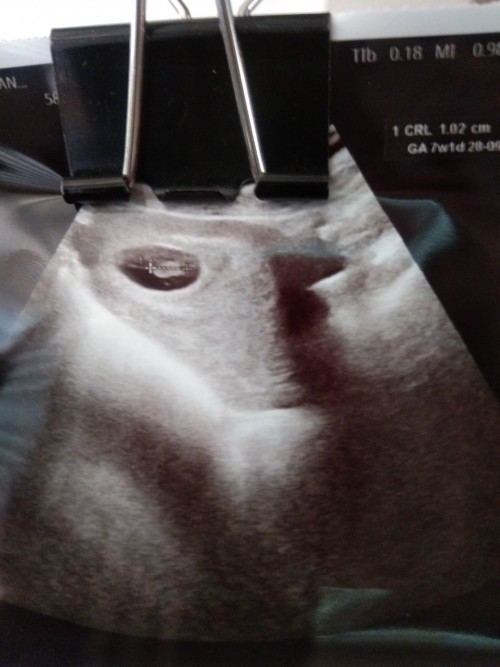

9w2dค่ะ น้องยังเล็ก

ตอน6w ค่ะ